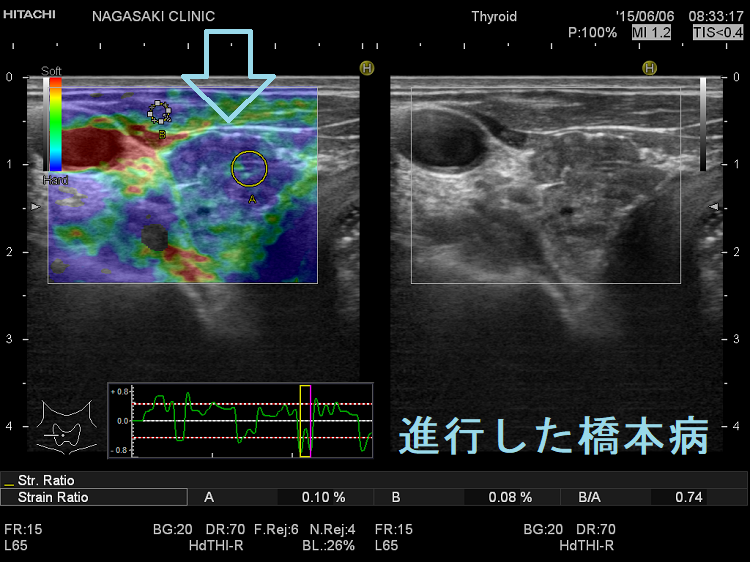

新たな試み;バセドウ病橋本病(慢性甲状腺炎)を採血前にエラストグラフィーで判別

バセドウ病橋本病(慢性甲状腺炎)を採血前にエラストグラフィーで判別しようとする試みがあります。[Assessment of Diffuse Thyroid Disease by Strain Ratio in Ultrasound Elastography. Ultrasound Med Biol. 2015 Nov;41(11):2884-9.]

典型的には(上)バセドウ病:全体的に (中)橋本病(慢性甲状腺炎):全体的に (下)亜急性甲状腺炎炎症部が・正常部が

になります。橋本病(慢性甲状腺炎)

1. 破壊され尽くした末期の状態

2. 線維化が進んだ状態

なら甲状腺組織が硬くなり、エラストグラフィーで全体的に青く見えます。しかし、破壊の程度が軽く、線維化が進んでいない状態ならが主体になります。

進行した橋本病 エラストグラフィー

進行した橋本病(慢性甲状腺炎):線維化が進んで硬くに見えます

橋本病(慢性甲状腺炎) エラストグラフィー

進行した橋本病(慢性甲状腺炎) エラストグラフィー